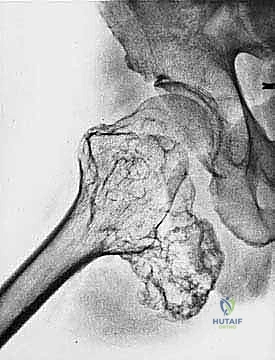

* ساركوما إيوينغ (Ewing Sarcoma): تصيب غالباً العظام الطويلة والحوض.

* الساركوما الغضروفية (Chondrosarcoma): تنشأ في الخلايا الغضروفية وتصيب البالغين وكبار السن.

| حدود الورم في الأشعة | واضحة، محددة بدقة (Sclerotic margin) | غير واضحة، متآكلة (Moth-eaten appearance) |

| اختراق قشرة العظم | نادر جداً | شائع جداً، يمتد للأنسجة الرخوة المحيطة |

الهدف الأول في جراحة الساركوما ليس فقط إزالة الكتلة المرئية، بل استئصالها مع طبقة من الأنسجة السليمة المحيطة بها لضمان عدم ترك أي خلايا مجهرية. تُصنف الهوامش الجراحية إلى:

- الاستئصال الواسع (Wide Resection): وهو المعيار الذهبي. يتم استئصال الورم مع طبقة من الأنسجة السليمة المحيطة به (العضلات، العظام). هذا ما يبرع فيه الدكتور هطيف لضمان الشفاء التام.